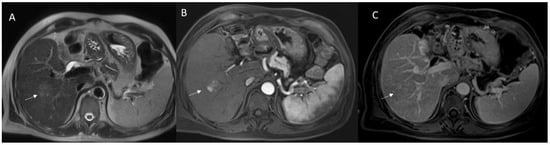

- Granata, V.; Fusco, R.M.; Catalano, O.; Filice, S.; Avallone, A.; Piccirillo, M.; Leongito, M.; Palaia, R.; Grassi, R.; Izzo, F.; et al. Uncommon neoplasms of the biliary tract: Radiological findings. Br. J. Radiol. 2017, 90, 20160561. [Google Scholar] [CrossRef] [PubMed]